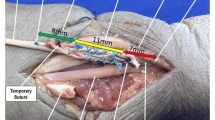

Continuous saline graft irrigation using syringes was performed throughout the preparation and mechanical testing to prevent drying. For the tests, an electro-mechanic two-columns universal testing machine (Instron 3367), equipped with a 30 KN load cell (Instron Systems, Norwood, Massachusetts), was used. Since the experiments carried out in this work required load comprised between 50 and 700 N, the accuracy of the load cell was verified to be within ± 0.5% of the reading in the above range, which is considered sufficient for the evaluations made in this work.

The final tendon configuration (see Fig. 2) was obtained while connecting the tendon to the testing machine. In particular, regarding the connection of the upper part to the testing machine crosshead, each graft was passed over a cylindrical steel rod of 5 mm diameter, connected to a clevis preliminary clamped on an Instron mechanical wedge grip, which in turn was connected to the 30 KN load cell (Fig. 1b, c) [25, 26].

All couplings between the various parts where axially tightened by threaded flanges, so as to eliminate any axial clearance. The lower end of the samples was fixed by a Zwick Roell wedge-screw grip, clamping the samples for a length of 2 cm. The lower grip was firmly connected to the test machine rig, again eliminating any possible axial clearance. In this way, the crosshead displacement during the test could account only for the grafts stretching and/or slippage on the lower clamp.

Grafts were fixed with a distance of 70 mm from the clamp to the rod, to simulate the femoral tunnel length (40 mm) and intra-articular space of the ACL (30 mm) that could be obtained with more recent femoral fixation devices (Fig. 1).

Non-absorbable sutures (No. 2 Ticron, Tyco, Waltham, MA) were used for graft preparation. Each suture was passed under a slight tensile load of the graft, to avoid permanent graft elongation, due to the slippage of the wire over the tendon tissue during loads [27, 28]. The diameter of each graft construct was measured before tests using a diameter measurement tool was used (Smith and Nephew, Androver, USA) and a Vernier caliper with ± 0.05 mm accuracy.

Each tripled graft was 9 cm long while the mean length of samples for each group from the rod to the clamp was 7.06 cm in Group I, 7 cm in Group II 6.87 cm in Group III, and 7 cm in Group IV. No differences in terms of graft diameter were observed among the 4 groups (> 0.05). All specimens completed phase 1 and phase 2 of the loading protocol (pre-conditioning and cyclical loading) and all graft failed during the final monotonic tensile load stage. In Group I, all samples failed at the level of the clamp; in Group II, rupture occurred at the level of the clamp in 75% of grafts and in the middle of the bundles in 25% of them.; in Group III and IV, 87.5% of the samples failed at the level of the clamp and in 12.5% failed in the middle of the grafts.